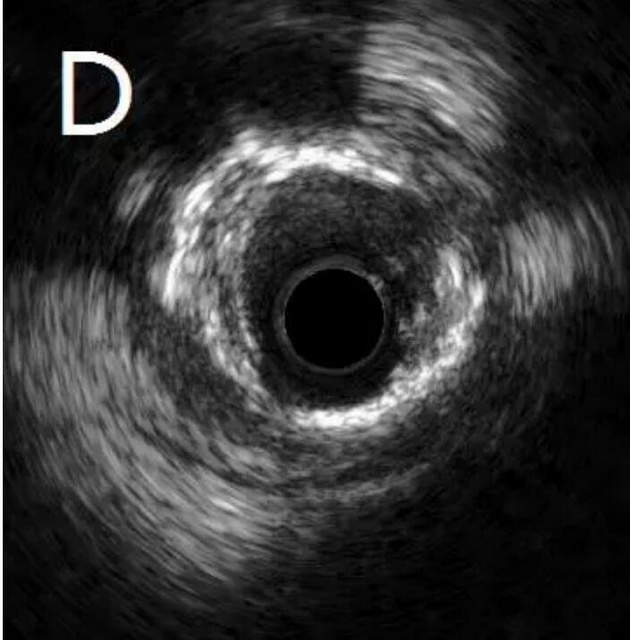

患者为77岁女性,因冠心病进行冠状动脉介入治疗,造影发现冠状动脉前降支不仅闭塞(图A),而且伴有钙化。通过不懈的努力,将闭塞的血管打开,但钙化处球囊无法将病变充分扩张(图B),意味着无法通过植入支架来维持血管管腔。于是采用血管内超声对病变处进行检测,显示病变处存在严重的360度环形钙化(图C、D)。